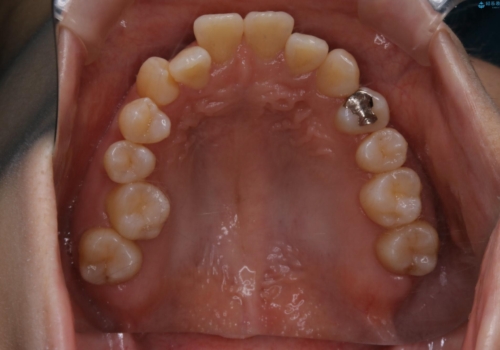

- 上の前歯は内側に入っていることが気になりご相談にいらした方です。インビザラインにて治療を行いました。

1週間でのマウスピース交換を指示していましたが、20時間以上使えない時があると不安との事で、2週間ごとの交換にしていました(実際はほとんど20時間以上使用できていたようです)。治療終了まで時間はかかりましたが、最終的に綺麗に並べることができ、大変喜んでいただけました。